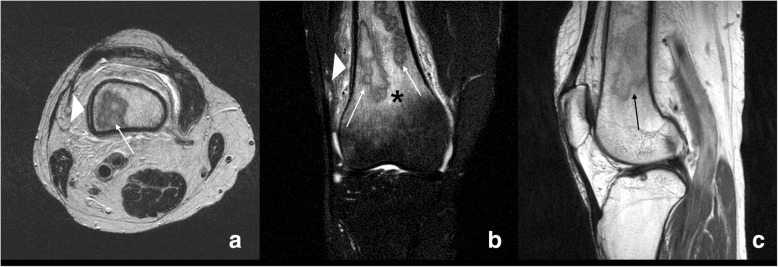

Fig. 2.

Preoperative MRI findings of the right knee. Axial (a), coronal (b), and sagittal (c) T2-weighted MRIs are shown. There were multifocal intraosseous lesions (arrows, 6.1 × 2 × 2 cm sized) at metaphysis and diaphysis of the distal femur. There was no destruction of cortical bone. However, double periosteal line, which suggesting periosteal reaction (arrow head, a and b), and marrow edema were found in the surrounding tissues (asterisk, b)

On the physical examination, an increased local heat in the proximal area of the right knee without an external wound, or draining sinus was confirmed. Body temperature was 38.8 °C. Laboratory test results showed the following: leukocytes 7260/μL (neutrophil 79.1%), absolute neutrophil count 4050, C-reactive protein (CRP) 21.26 mg/L, and erythrocyte sedimentation rate (ESR) 72 mm/h. We conducted synovial fluid analysis on the fluid extracted from the right knee joint. Synovial fluid analysis revealed a white blood cell count of 870/mm3, a polymorphonuclear leukocyte of 45%, and no crystals were found. Anteroposterior and lateral radiography of the right knee revealed multifocal osteolytic changes in the distal metaphysis area of the right femur. The lesion had an irregular margin but no sclerotic rim (Lodwick classification type 1B). There was no definite destruction of cortical bone. However, a subtle cortical thickening lesion suggesting solid type of periosteal reaction was found at superior aspect of lateral femoral condyle (arrow head, a) (Fig. 1). The axial (a), coronal (b), and sagittal (c) T2-weighted magnetic resonance imaging (MRI) of the right knee, which were previously performed at another hospital (with lacking information of T1 weighted and enhanced image), are shown in Fig. 2. Multifocal intraosseous lesions (6.1 × 2 × 2 cm) at metaphysis and diaphysis of the distal femur were observed with no destruction of cortical bone. However, double-contour periosteal line, which suggesting periosteal reaction (arrow head, A and B) at lateral aspect, and marrow edema were found in the adjacent tissues (asterisk, B). Considering the patient’s age, location of the lesion, margin, and absence of cortical destruction, we suspected osteomyelitis rather than a bony malignancy.